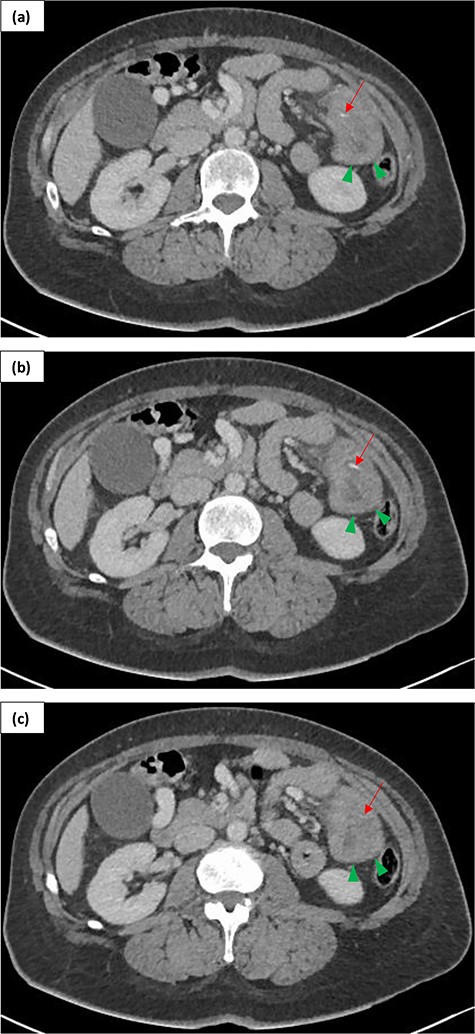

Admission computed tomography (CT) demonstrated thickened bowel loops in the left flank, related to the enteroenterostomy (Fig. 1). There was no mesenteric swirl, nevertheless, bowel thickening, venous compression and mesenteric oedema, in context of previous RYGBP, were concerning for bowel compromise secondary to internal herniation. It was felt that the probability of internal hernia in context of previous RYGBP, patient’s age and lack of significant past medical history was much higher than bowel ischaemia due to another reason. Linear high attenuation (representing the fishbone) was noted but presumed to be suture line at the enteroenterostomy (Fig. 1).

Contrast enhanced (portal phase) CT of a 54-year-old female presenting with LIF peritonism in context of previous RYGBP over 10 years ago. Serial images in axial plane (a, b, c) demonstrate thickened small bowel loops in the left flank (green arrowheads) and a fishbone as a linear hyper density (red arrow).